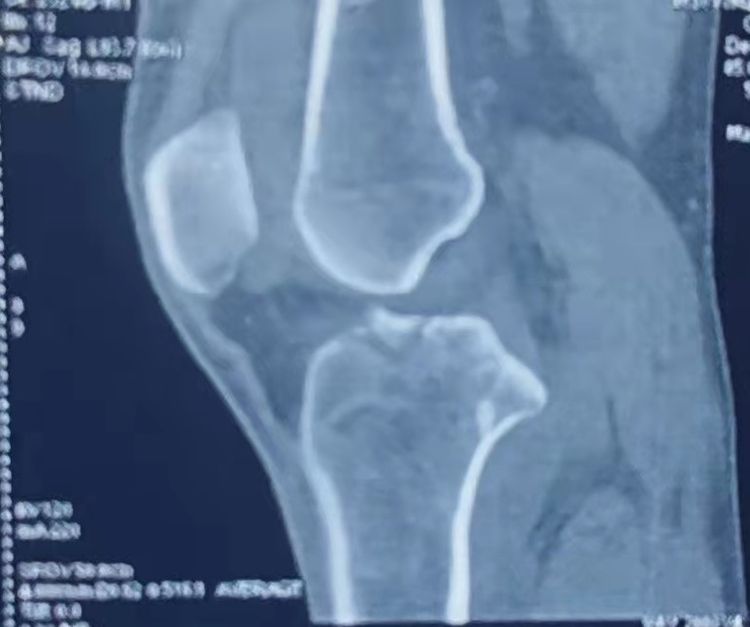

左膝正侧位DR:左膝前交叉韧带胫骨止点撕脱骨折,内侧胫骨平台骨折,均未见明显移位。

左膝CT

初步诊断:1、左膝ACL胫骨止点撕脱骨折 2、左膝胫骨平台骨折(Schatzker Ⅰ型) 3、左膝关节积液